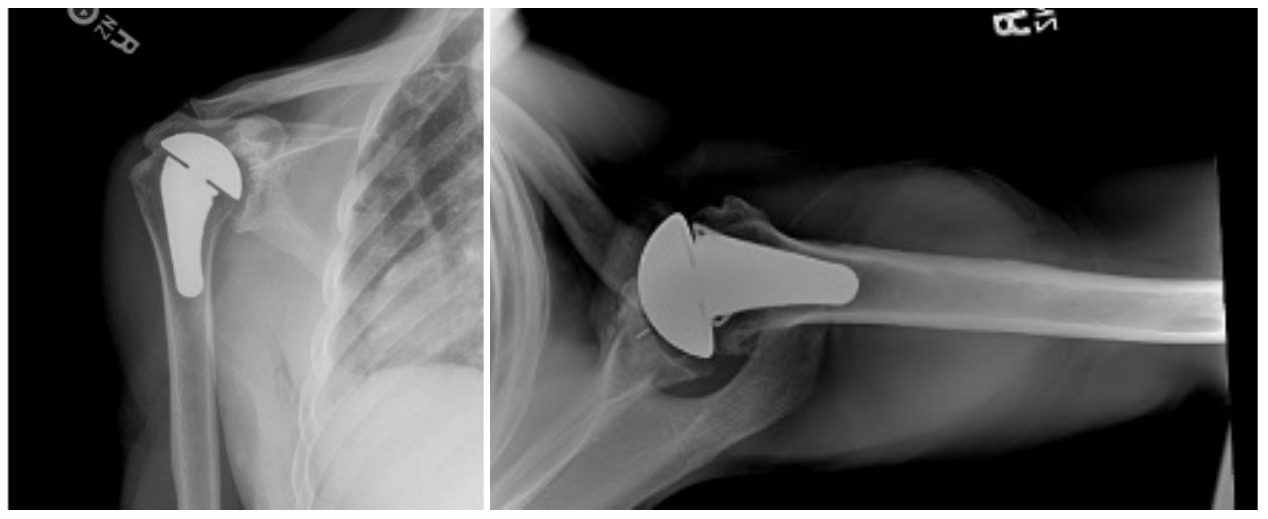

Case one is a 58-year-old male who is an avid golfer with long standing right shoulder pain. Surgical history includes previous Bristow procedure 30 years prior. Current Subjective Shoulder Value (SSV) is 30% and pain is 8/10 at baseline. Active range of motion was 110° of forward flexion, -10° of external rotation and interna rotation to the lateral buttock. Radiographs (Figure 1) and computed topography (CT) scan (Figure 2) show retained implants with loss of joint space, glenoid retroversion, and significant posterior humeral head subluxation. The patient had failed conservative management and was indicated for arthroplasty. Due to significant posterior bone loss and retroversion, an augmented anatomic component was selected for this patient. Radiographs at one year show a well seated glenoid component with restoration of the joint line and a centered humeral head (Figure 3). At five years, SSV had improved to 95% with excellent clinical motion (Figure 4).